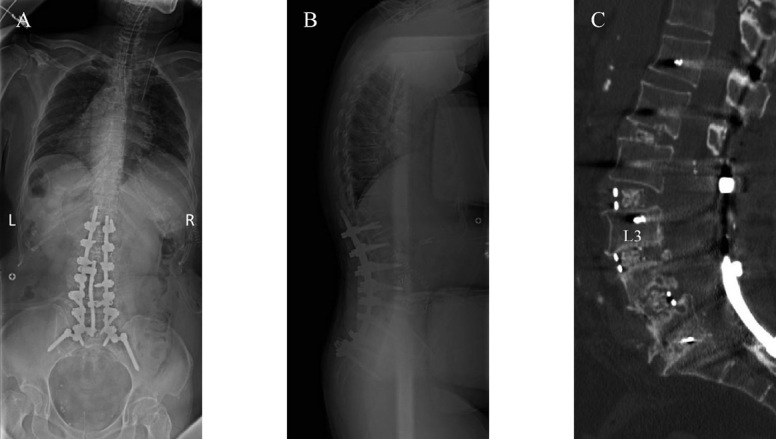

Postoperative radiographs and CT

Fig. 2A, 2B: Intraoperative prone posteroanterior (A) and lateral (B) radiograph.

Fig. 2C: Sagittal view of CT.

Radiographs showed that the global alignment error with the pelvic incidence (PI) was 53°, lumbar lordosis (LL) was 16°, lower lumbar lordosis (LLL) was 5°, C7-SVA was 125 mm, and the degenerative scoliosis with the degree of lumber scoliosis was 33° (Fig. 1A, B). CT myelography and MRI revealed severe endplate degeneration, spondylolisthesis, and spinal canal stenosis of the L3/4 and L4/5 (Fig. 1C, D). The patient underwent LLIF followed by posterior fusion from T12 to the iliac, total laminectomy from the L2 to the sacrum, and grade 2 osteotomy from the L2/3 to L5/sacrum. Pure titanium rods (6 mm) were used, while additional rods were used to increase the posterior fixation strength. Rib bone and β-TCP were used as grafted bones in the LLIF cages (Fig. 2).